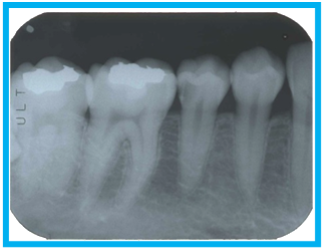

デジタル撮影

限られた数本の歯を高精細に写し出す局所撮影で、虫歯や根尖(こんせん)病変、歯槽(しそう)骨の詳細な評価に適しています。